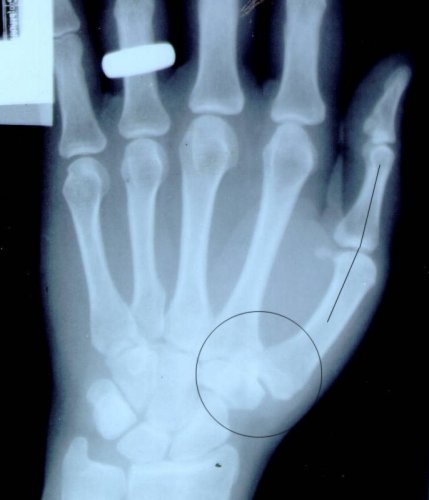

This is an x-ray of Betty Lou's left hand taken in 1985; normal at that time.

This x-ray reveals the recent damage. The circle highlights the affected area – most of the trapezium seems to have turned into sand. And the line shows how far the proximal phalange sometimes could move out of a normal position.